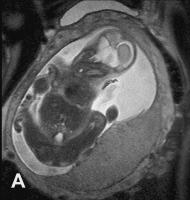

Abbildung 2a-b: SSW 30, Fetus mit Balkenagenesie, A. Medianes Schnittbild: Fehlender Balken, radiäre Gyrierung an der Medialfläche der Hemisphäre. Der Aquädukt und die Vierhügelplatte unauffällig. Der Hirnstamm zeigt dorsal dünklere Signale als ventral, was der normalen, dort bereits in dieser SSW vorhandenen Myelinisierung entspricht. Im Profil geringe Retrognathie. B. Frontales Schnittbild. Typische Konfiguration der Seitenventrikel, die auf Grund der medial der Vorderhörner erkennbaren Probst’sche Bündel weit auseinander stehen. In den erweiterten Temporalhörnern erkennt man eine nahezu senkrecht stehende Hippocampusformation, was einer Malrotation entspricht. Die Gyrierung ist symmetrisch, eine pathologische Konfiguration des frontalen Anteils des Gyrus cinguli, wie sie im Rahmen der Balkenagenesie zu erwarten ist, besteht. Intrazerebral ist die zelldichtere und daher dünklere Stammganglienregion von der helleren weißen Substanz, die ebenfalls in entwicklungsbedingt unterschiedliche Graustufen gegliedert ist, abgrenzbar.